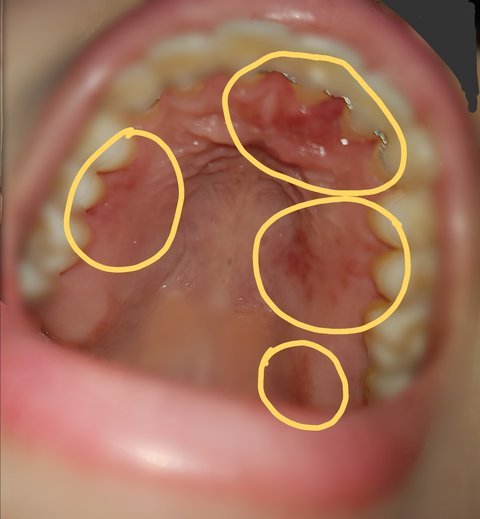

그리고 낮잠을 자고 일어나니, 가운데 윗 잇몸도 심각하게 붓고 오른쪽 윗 잇몸은 벗겨지고 있었으며, 전체적으로 발갛게 부어있었습니다.

다음은 피해사진입니다.

#피해자1

-4월 30일 월요일 낮

-4월 30일 월요일 밤

-5월 1일 화요일 아침